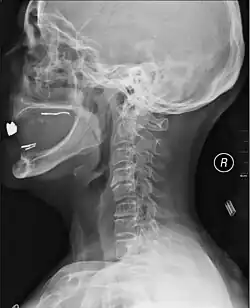

| MRI of a fractured and dislocated cervical vertebra (C4) in the neck that is compressing the spinal cord | |

A radiographic evaluation using an X-ray, CT scan, or MRI can determine if there is damage to the spinal column and where it is located.[10] X-rays are commonly available[89] and can detect instability or misalignment of the spinal column, but do not give very detailed images and can miss injuries to the spinal cord or displacement of ligaments or disks that do not have accompanying spinal column damage.[10] Thus when X-ray findings are normal but SCI is still suspected due to pain or SCI symptoms, CT or MRI scans are used.[89] CT gives greater detail than X-rays, but exposes the patient to more radiation,[91] and it still does not give images of the spinal cord or ligaments; MRI shows body structures in the greatest detail.[10] Thus it is the standard for anyone who has neurological deficits found in SCI or is thought to have an unstable spinal column injury.[92]